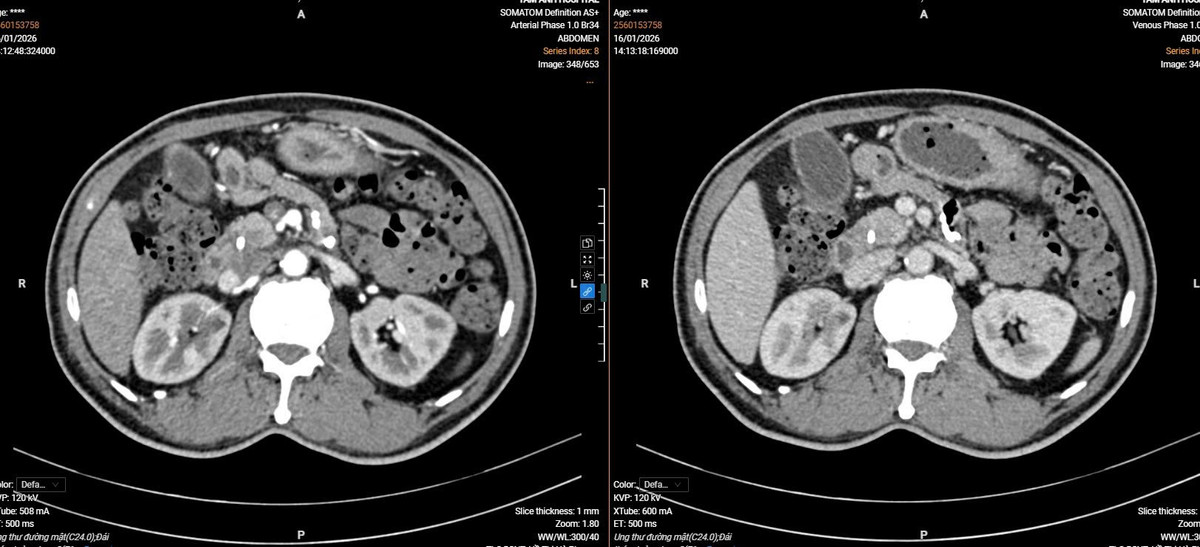

Hình ảnh nội soi u bàng quang vị trí sát lỗ niệu quản trái kích thước 2cm, có chỉ định phẫu thuật nội soi cắt u bàng quang sớm để chẩn đoán tế bào học - Ảnh BVCC

ut-bang-quang-1.jpg

Kết quả cắt lớp vi tính của người bệnh - Ảnh BVCC